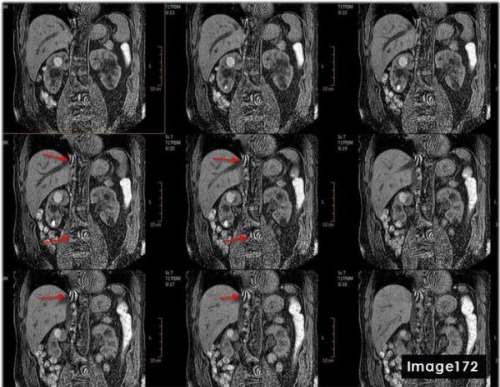

The red arrows in Image 172 are indicative of which type of MRI artifact?

A. Wraparound

B. Annefact

C. Dielectric effects

D. Parallel Imaging

To correct for the central aliasing artifact shown in Image 172, which is characteristic of parallel imaging reconstruction error, the MRI technologist would:

A. Reduce parallel imaging factor

B. Increase parallel imaging factor

C. Increase FOV

D. A and/or C

D. A and/or C (Reduce parallel imaging factor and/or Increase FOV)